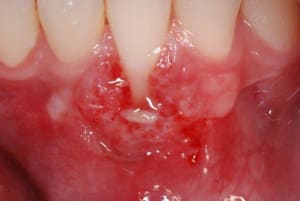

IMG_5605__Desktop_Resolution__a0ooq3.jpg